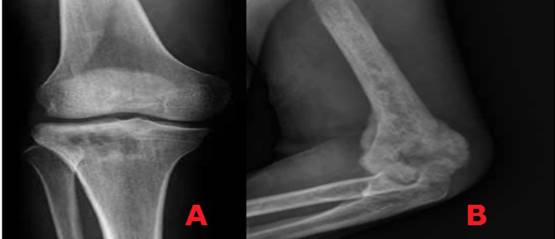

La radiografía es la mejor: modalidad de elección en el estudio de tumores óseos. Esta técnica permite generar la densidad de todos los puntos de una lesión en una imagen de dos dimensiones. (21) Los aspectos a evaluar al abordar una radiografía cuando se analiza una lesión ósea incluyen: localización, márgenes, reacción perióstica, tamaño, mineralización y compromiso de tejidos blandos. (22

Localización

Al evaluar una lesión ósea se deben tener en cuenta la localización de la lesión en el esqueleto y la ubicación específica de la lesión en el hueso afectado. Si se trata de una lesión central, excéntrica o yuxtacortical y si es una lesión única o múltiple La consideración de estos factores ayudará a reducir los diagnósticos diferenciales. (22

Características del borde

La evaluación de los márgenes de la lesión es crucial para determinar si ésta es de crecimiento lento (posible benigno) o de crecimiento rápido (agresivo). Las lesiones de crecimiento lento tienen un borde esclerótico bien definido; mientras las lesiones agresivas o malignas tienen bordes muy mal definidos e irregulares, con mínimo o sin esclerosis reactiva. (22